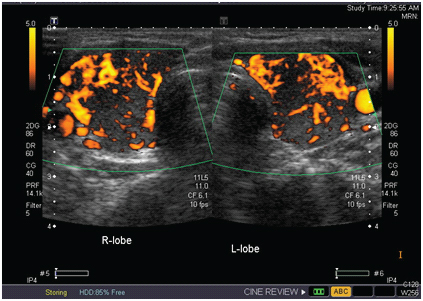

During evaluation at the time of present admission, she was a thin build lady with hyper-pigmentation of the oral mucosa, palmar creases of both hands and extensor aspects of both arms with no vitiligo. Her supine neck examination showed a WHO grade –II diffuse thyromegaly and there were no obvious signs of thyrotoxicosis (fine tremor, prominence of eye balls) and there was no thyroid bruit. Her supine blood pressure was 100/70 mmHg and on standing, the blood pressure was 90/60 mmHg and pulse was 120/minute. In view of her symptoms suggestive of adrenal crisis, she was immediately started on injectable hydrocortisone on an outpatient basis. She was post menopausal by three years. At the time of admission to our hospital her random serum cortisol was of 0.71μg/dl (normal 5-27μg/dl) and plasma ACTH of 560 pg/ml (Normal 0-46pg/ml). The investigations for thyroid status showed TSH –0.004μIU/ml (normal: 0.3-4.5), T4 –30 μg% (8-12), and FT4 –6.82 ng% (0.8-1.8) which was suggestive of thyrotoxicosis. Her thyroid receptor antibody (TSI) level was 8.1 μ/L (Normal 1-5), anti-peroxidase autoantibody (anti –TPO) was 514 IU/ml (<50) by ELISA. Her ultrasound of thyroid showed a diffuse enlargement of both lobes with an increased vascularity [Table/Fig-1] and radioiodine uptake study showed increased radioiodine uptake at 1 hours - 70%; 6 hours-92% and 24 hours -90% with diffuse uptake of both lobes [Table/Fig-2] suggestive of Graves’ thyrotoxicosis. Other investigations revealed FSH of 71.1mIU/ml, electrolyte sodium of 136 mEq/L, potassium 4.0 mEq/L, creatinine of 0.45 mg% (normal 0.5- 1.4) and Vitamin B12 of 340.6 pg/ml (normal 200-950) .

USG doppler image showing an increased internal vascularity in both lobes of the thyroid.